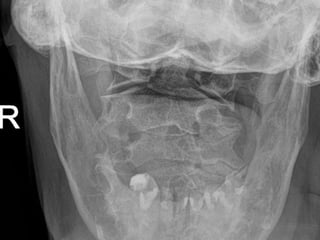

69 year old man with C2

fracture

Admitted for CHF and while

hospitalized was walking to

the bathroom at night and

fell on to head lacerating

forehead. Staff responded

to his calls for help and

immediately ordered a

cervical CT due to

complaints of new neck

pain

PMH: COPD, CHF,

anxiety/dep, liver cirrhosis,

cognitive decline,

pulmonary HTN,

SH: retired lives in group

home

69 year oldman with C2 fracture Admitted for CHF and while hospitalized was walking to the bathroom at night and fell on to head lacerating forehead. Staff responded to his calls for help and immediately ordered a cervical CT due to complaints of new neck pain PMH: COPD, CHF, anxiety/dep, liver cirrhosis, cognitive decline, pulmonary HTN, SH: retired lives in group home